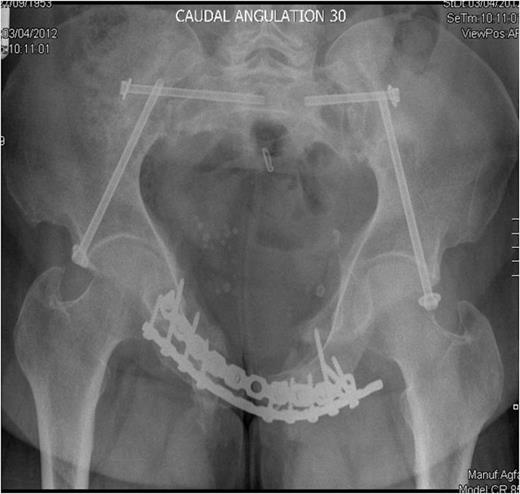

Following admission, routine blood parameters (including bone profile) were all normal and a pelvic MRI scan out-ruled any intra-pelvic soft tissue lesions. Open reduction and internal fixation of her anterior pelvic ring was undertaken through a Stoppa approach, both rami fractures were reduced and plated anteriorly and superiorly. At this time bone and soft tissue samples from the anterior ring were sent for analysis. Following reduction and fixation of her anterior pelvis, intra-operative fluoroscopy revealed that her posterior injuries were in an acceptable position. A 3cm long vertical incision was made over both anterior inferior iliac spines and supra-acetabular screws were placed from the anterior inferior iliac spines to the posterior inferior iliac spines to fix the bilateral iliac wing fractures. Finally bilateral percutaneous sacroiliac screws were inserted to stabilise the sacro-iliac joints.

Inlet radiograph at 16 months post surgery demonstrating solid fixation and bony healing

Post-operative recovery was uneventful. Bone and soft tissue biopsies showed no abnormalities. She was kept non weight bearing for 12 weeks. Subsequent dual energy X-ray absorptiometry scanning revealed mild osteopenia for which she is being managed medically. She began full weight bearing at 3 months post surgery. Final follow-up at 16 months demonstrated that the fractures had healed, and the patient was pain free and mobilising unaided (Fig. 3 & 4).

Outlet radiographs at 16 months post surgery demonstrating solid fixation and bony healing